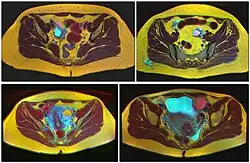

Ovarian cysts are usually diagnosed by pelvic ultrasound, CT scan, or MRI, and correlated with clinical presentation and endocrinologic tests as appropriate.[15] Ultrasound is the most important imaging modality, as abnormalities seen in a CT scan sometimes prove to be normal in ultrasound.[5][8] If a different modality is needed, then MRIs are more reliable than CT scans.[5]

Histopathology

In case an ovarian cyst is surgically removed, a more definite diagnosis can be made by histopathology:

| Type | Subtype | Typical microscopy findings | Image |